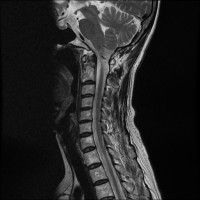

목,허리 디스크 엠알 판독.....

경추 요추 디스크 둘다 있는 상태고 경추몇번에서 몇번사이 요추몇번에서 몇번사이인지 알려주세요

목

• 2번 째 사진